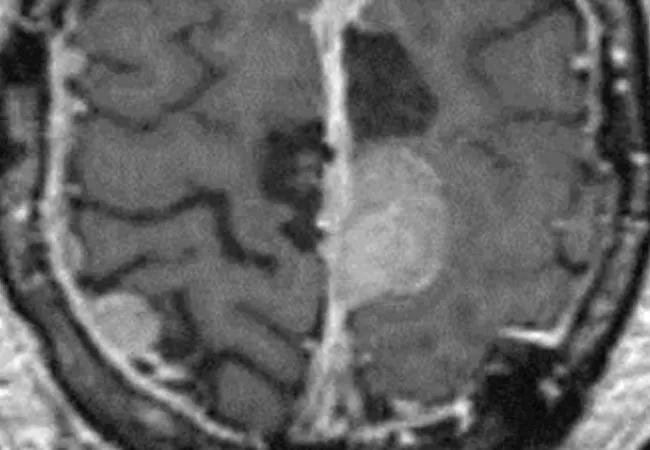

brain scan showing meningioma